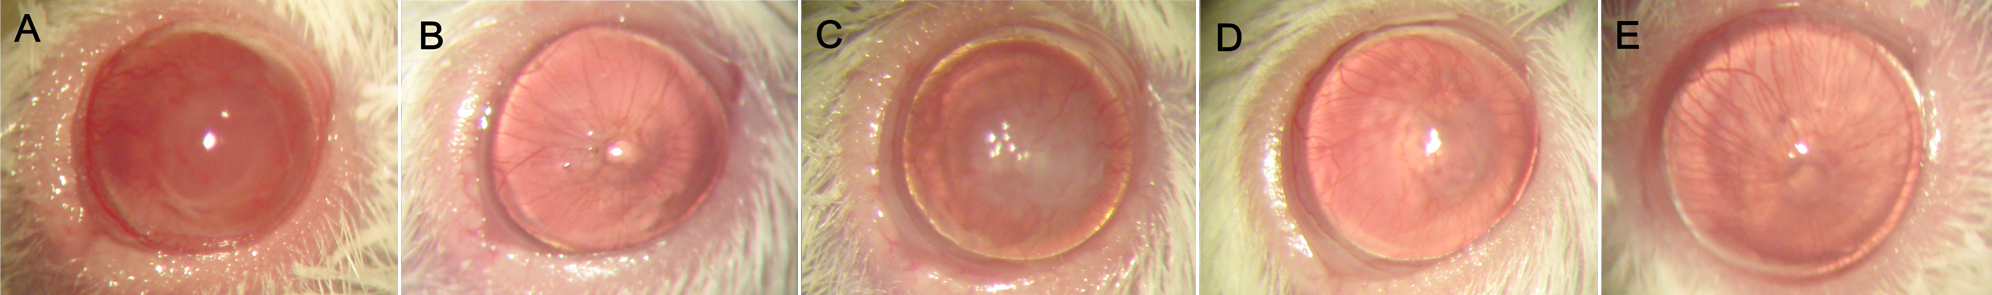

Figure 2. Opacity, edema and

neovascularization of corneal grafts were observed. A:

Ccontrol group on postoperative day 14. B: Topical 1% CsA group

on postoperative day 30. C: Topical 0.1% FTY720 group on

postoperative day 14. D: Topical 0.3% FTY720 group on

postoperative day 14. E: Topical 0.5% FTY720 group on

postoperative day 30.